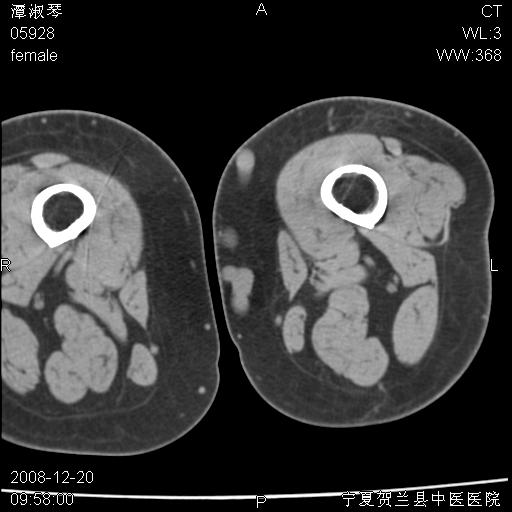

标题: CT17526:请各位看看是啥?

左胫骨下端松质骨及髓腔内可见点片状高密度灶,骨皮质无明显膨胀及变薄。病变范围较长。支持骨梗死,退行性骨关节病,膝关节积液

支持骨梗死,退行性骨关节病,膝关节积液.

左股骨下段骨梗死。双膝退变。